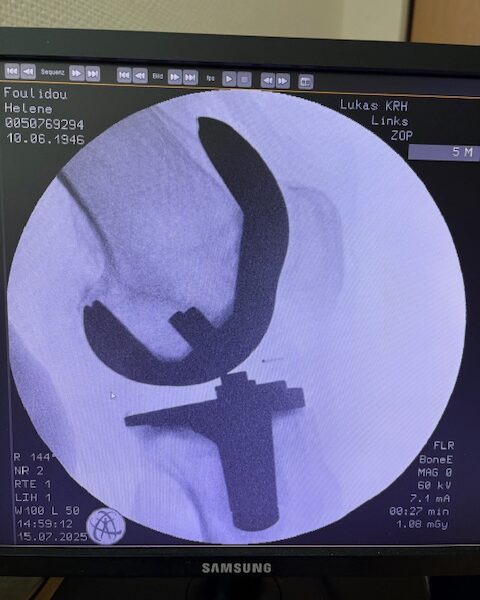

Η επέμβαση πραγματοποιήθηκε με ρομποτικά υποβοηθούμενη τεχνική, κατά την οποία το ρομποτικό σύστημα με καθοδήγησε με ακρίβεια χιλιοστού σε κάθε στάδιο.

Έτσι εξασφαλίστηκε η ιδανική τοποθέτηση των εμφυτευμάτων, η αποκατάσταση του μηχανικού άξονα και η διατήρηση των μαλακών ιστών.

Τα εμφυτεύματα που χρησιμοποιήθηκαν στο γόνατο της ασθενούς είναι της Aesculap: E-Motion Pro, μηριαίο μέγεθος 4, κνημιαίο μέγεθος 4, με ενθέμα (inlay) 10mm.

Η επέμβαση ολοκληρώθηκε χωρίς επιπλοκές, με ελάχιστη απώλεια αίματος και ταχεία κινητοποίηση της ασθενούς.